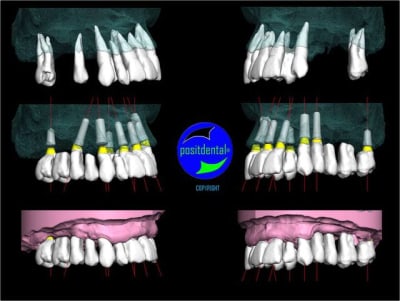

Montage esthétique ou wax-up 3D

S.I.A.O.